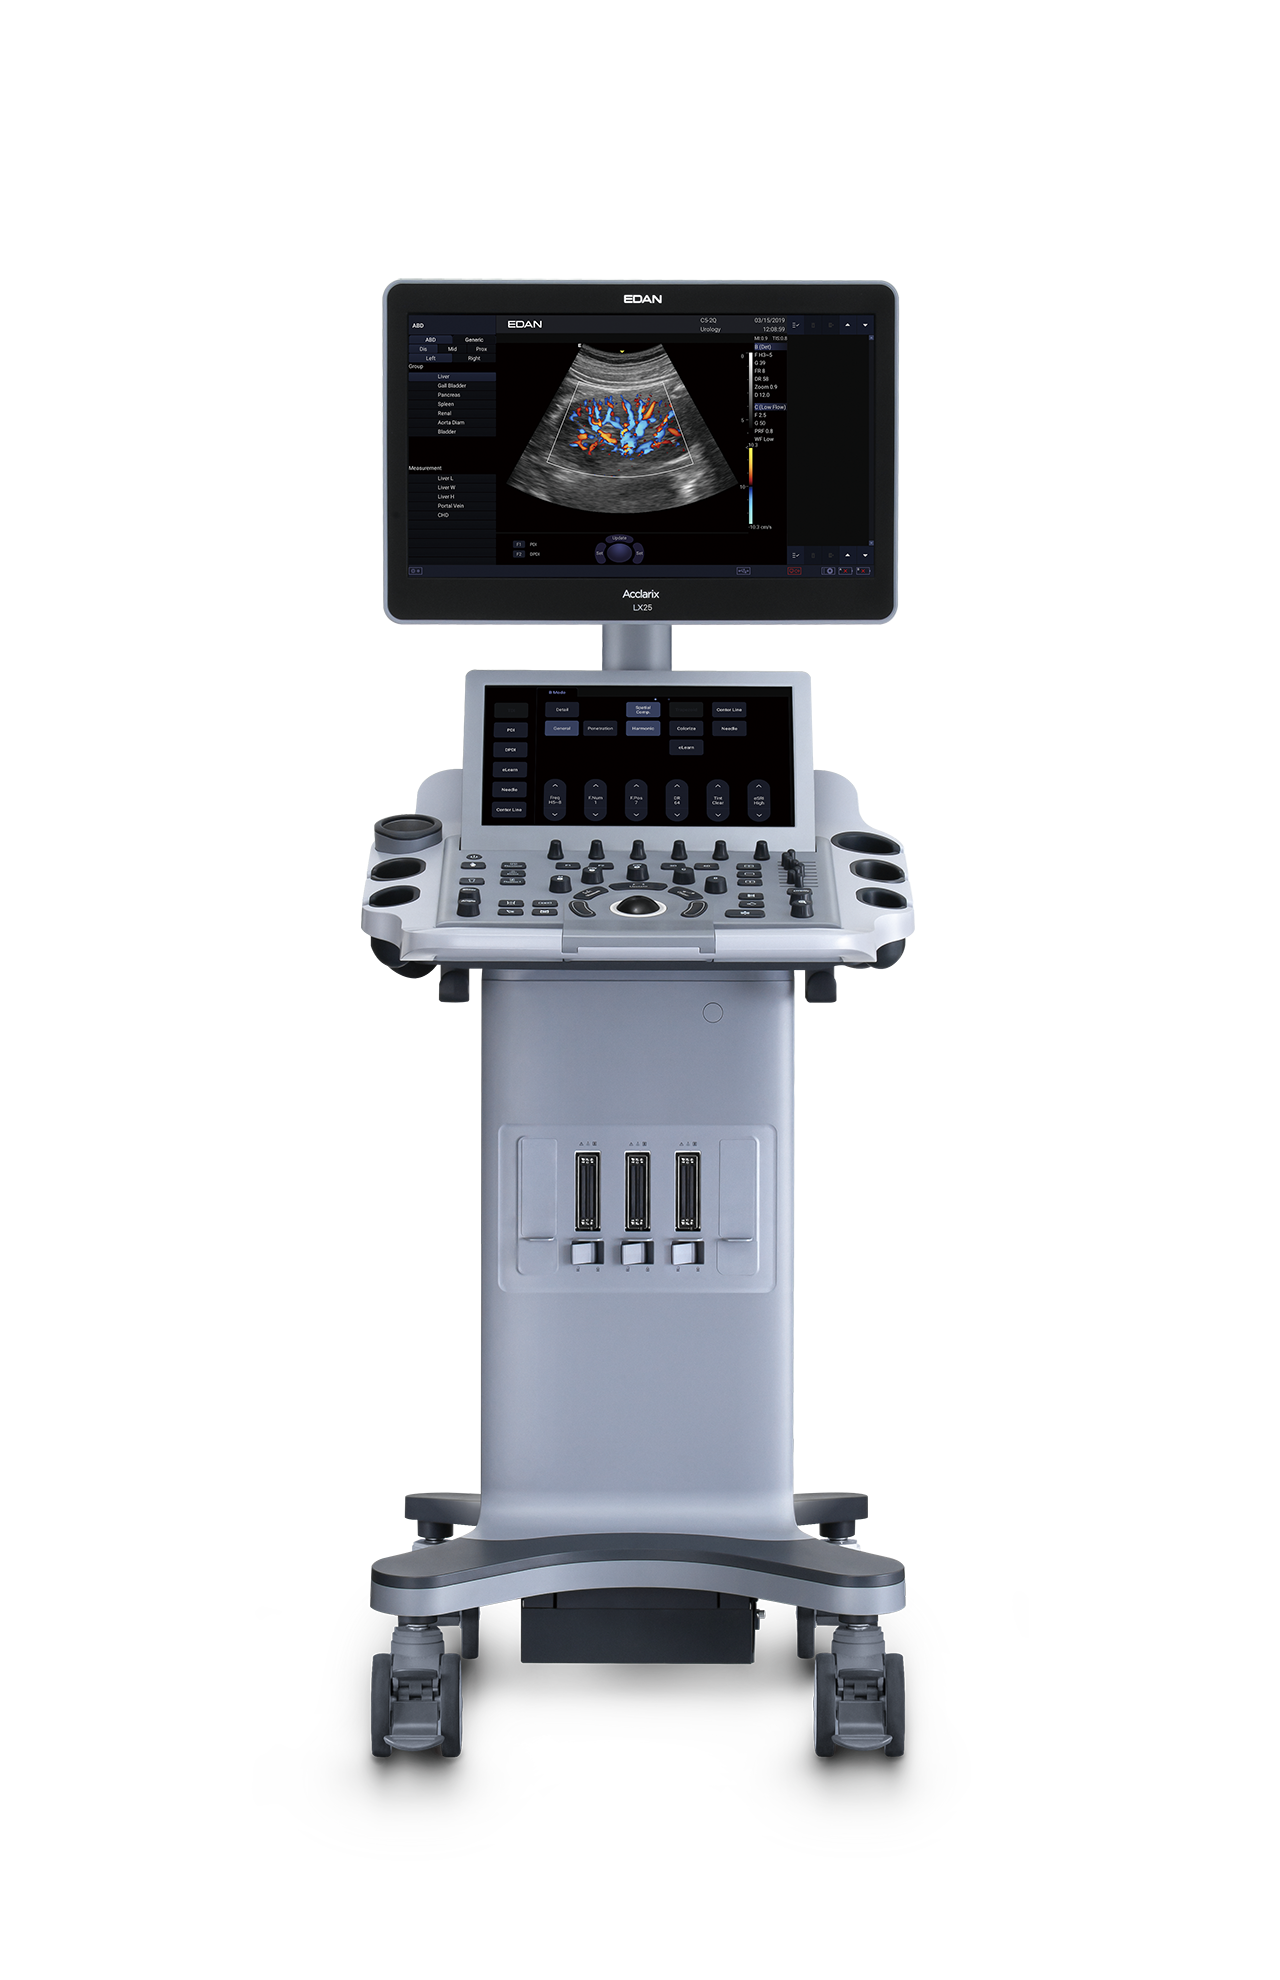

Ecógrafo Estacionario EDAN Acclarix LX25

Ecógrafo Estacionario EDAN Acclarix LX25

- Monitor LCD de 21.5″ HD con ángulo de visión multidimensional.

- Pantalla táctil de alta sensibilidad de 14″ que permite un funcionamiento eficaz.

- Diseño de calentador de gel.

- Configuración de 3 puertos para transductores.

- Diseño de ajuste de altura ergonómico.

- Baterías de respaldo y tiempo 2h de exploración continua.

Gracias a la innovadora tecnologia EDAN TAI, ya las múltiples tecnologías de procesamiento de

imágenes, Acclarix LX25 puede mostrar perfectamente la imágen de ultrasonido en diferentes

modos. ayudando al ecografista a realizar un diagnostico más preciso

La arquitectura de alta fidelidad y alto número de canales da como resultado una magnífica resolución

de los detalles, especialmente en profundidad.

| Peso | 55 kg |

| Dimensiones | 66 × 54 × 144 cm |